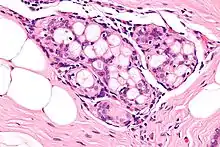

| Micrograph of collagenous spherulosis with the characteristic histomorphology - intratubular eosinophilic material with a spoke-like arrangement. H&E stain. | |

Collagenous spherulosis is characterized by a tubular/cribriform architecture with intratubular eosinophilic material that classically is arranged like the spokes of a wheel ("radial spikes"). There is usually no mitotic activity, and two cells populations (epithelial & myoepithelial) are present, like in benign breast glands.

The lesions are typically small (less than 50 spherules per lesion, less than 100 micrometers in size) and may be multifocal.